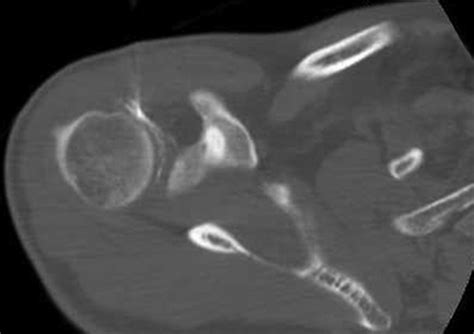

Accurately diagnosing conditions affecting the rotator cuff interval requires a combination of physical examination and advanced imaging. Physicians typically begin with clinical tests to isolate the function of the biceps tendon and the rotator cuff muscles. However, because the interval is deep, imaging is vital for a definitive diagnosis.

Magnetic Resonance Imaging (MRI) The gold standard for visualizing soft tissue, ligamentous thickening, and interval tears.